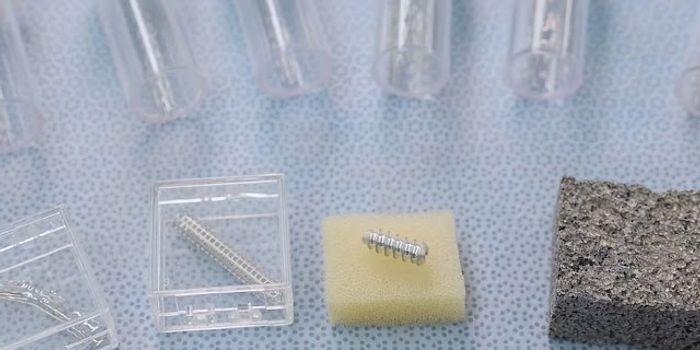

JAN 25, 2024Drug Discovery & DevelopmentDeveloping new pharmaceuticals is a complex and costly process that requires innovation and efficiency. High-throughput ...

JAN 31, 2023Plants & AnimalsBead mill homogenization is a fast technology for automatically preparing a wide variety of samples – up to 96 in ...